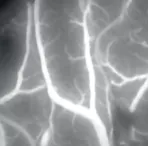

雙熒光技術(shù),實(shí)時(shí)了解更多血流和組織結(jié)構(gòu)信息

FL800 熒光

使用FL800術(shù)中影像血管造影術(shù)模塊實(shí)時(shí)觀察血流情況,在血管手術(shù)期間目視評(píng)估血管的通暢性。